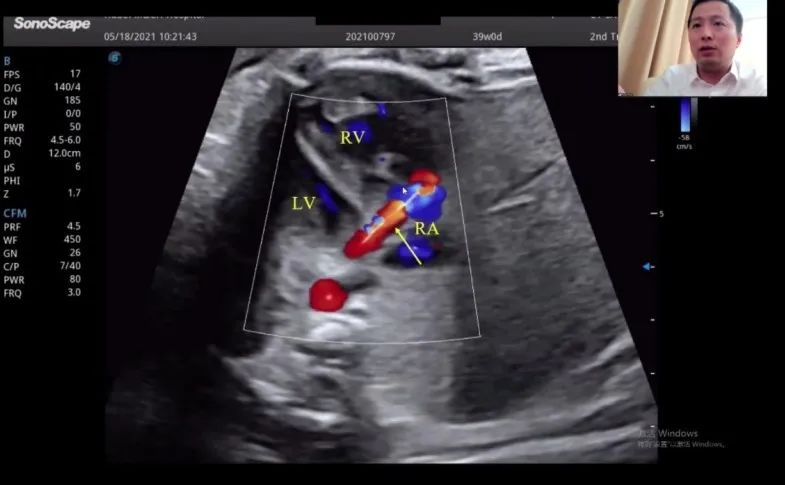

湖北省婦幼保健院的趙勝教授在會(huì)上帶來(lái)了胎兒冠狀動(dòng)脈瘺超聲診斷研究的分享。趙教授表示,冠狀動(dòng)脈瘺在妊娠晚期可通過(guò)超聲檢查顯示出來(lái),經(jīng)線圈栓塞或冠狀動(dòng)脈瘺術(shù)后,進(jìn)一步的臨床過(guò)程通常較為順利。